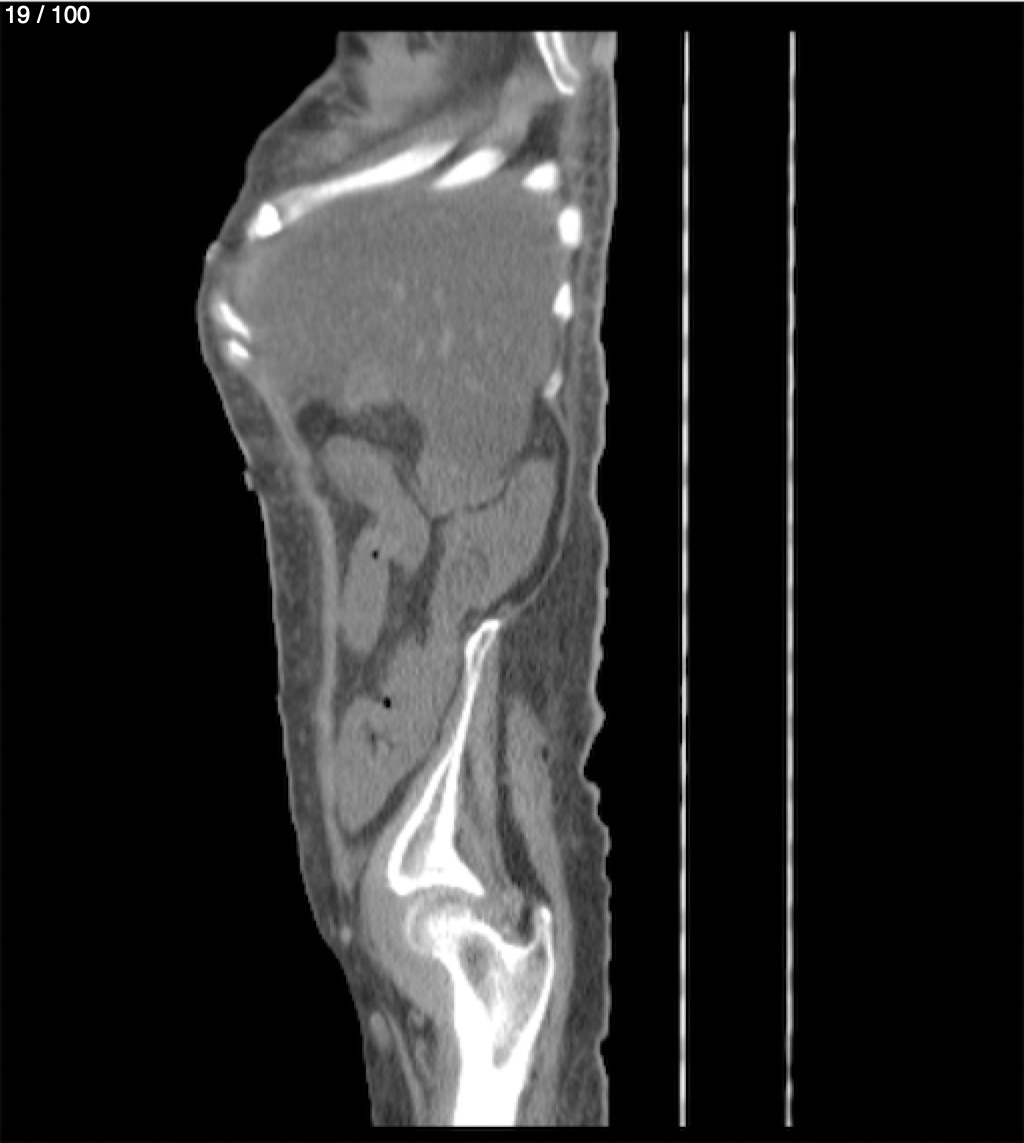

Hilda Geronimo Mendez 60A - T.C Abdomen Simple